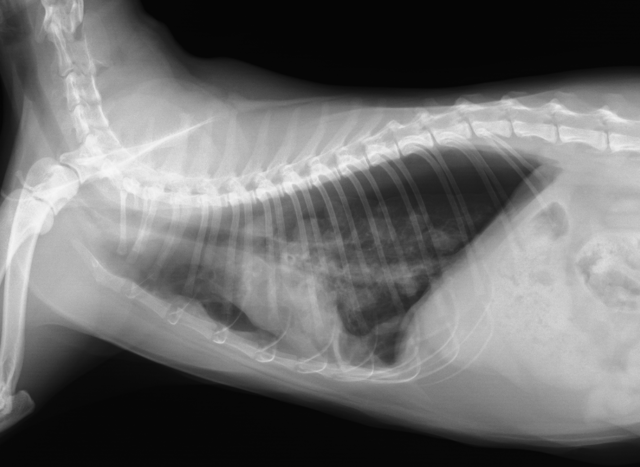

また胸部のレントゲンで写真のような肺の腫瘤性病変を確認し、糞便および気道分泌物中からの虫卵の検出で確定診断を行います。

レントゲンで見られるリング状陰影は、肺吸虫を包む虫嚢であり本疾患に特徴的な所見となります。